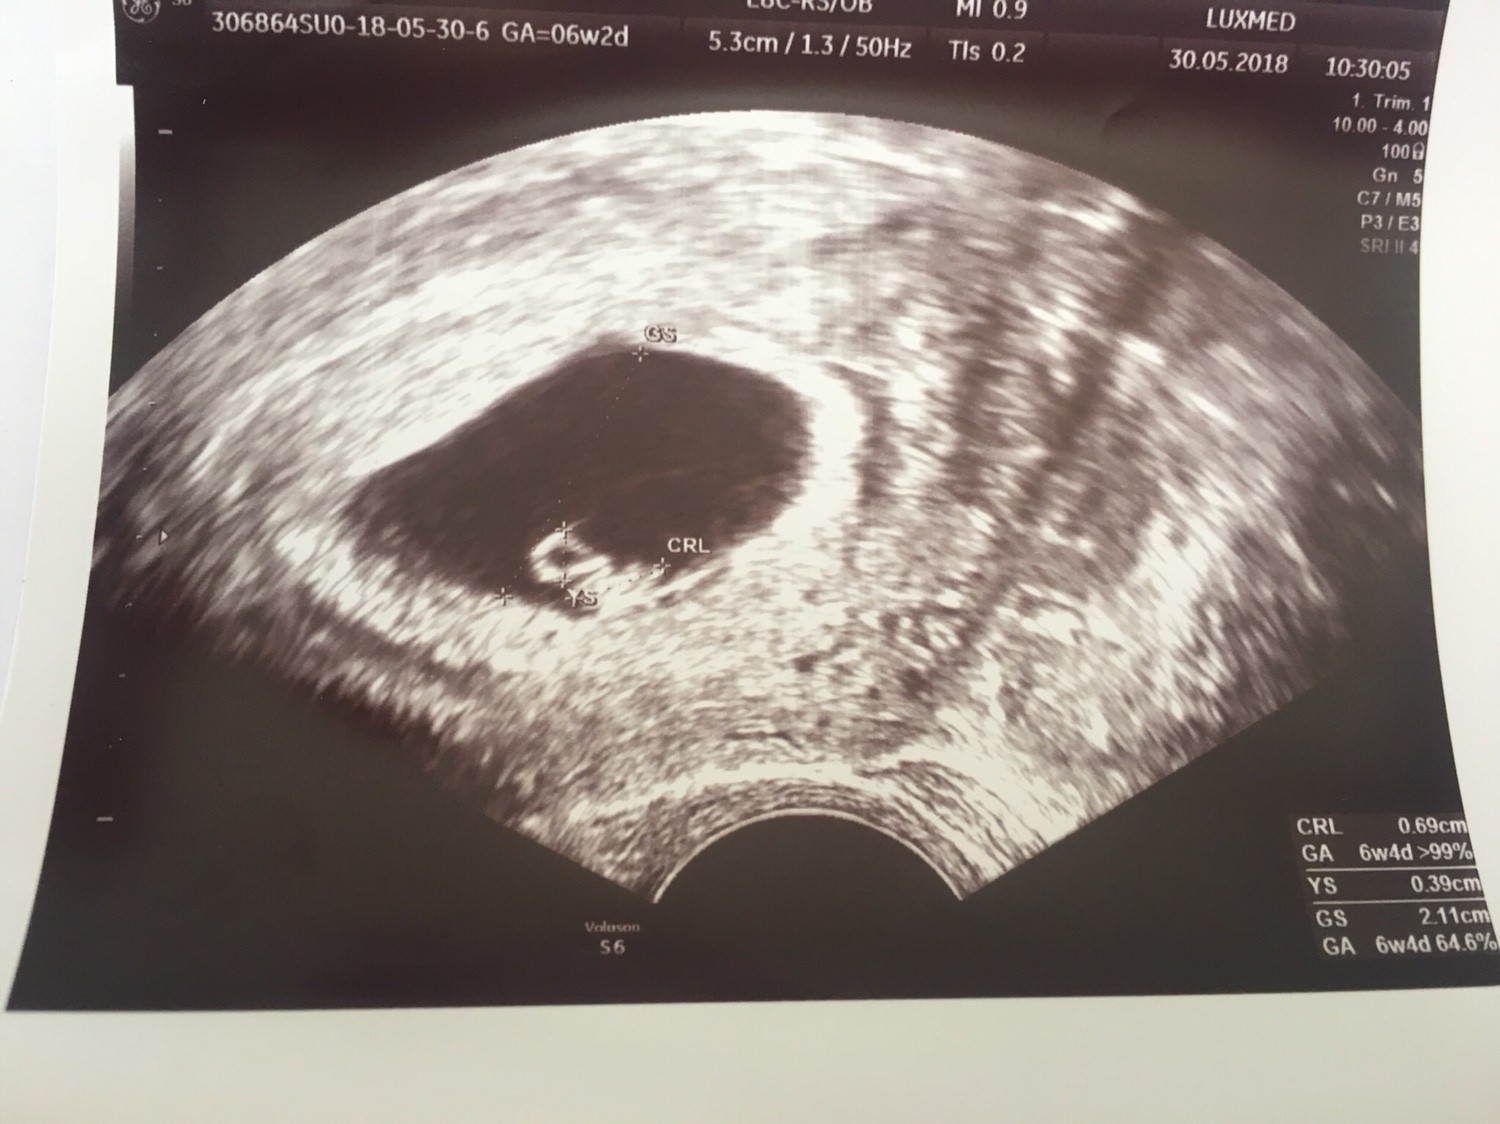

Hej dziewczyny [emoji4] ja dziś po pierwszym usg i jest dzidzia z serduszkiem [emoji173]️

Jeszcze malutka, bo to 6 tydzień, ale tak bardzo się cieszę [emoji4]

IMG_2305.JPG

• IMG_2305.JPG

265,7 KB · Wyświetleń: 422